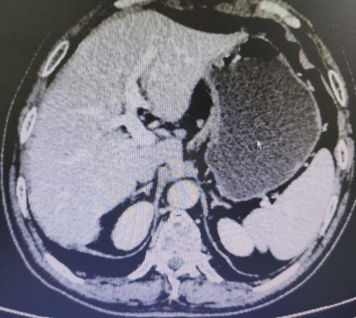

Abdominal CT films (2 sheets) on March 3, 2020